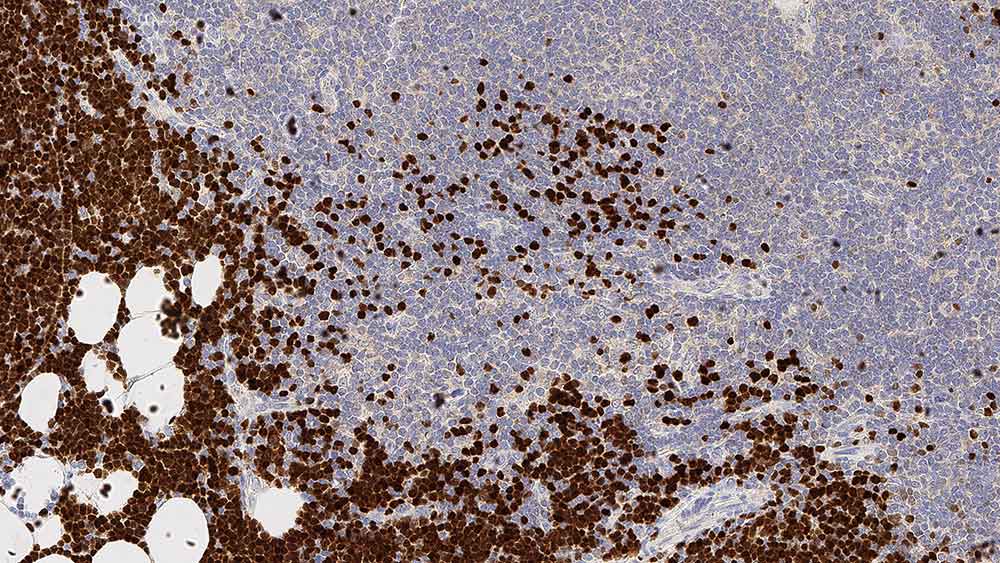

Human thymus: immunohistochemical staining for Terminal Deoxynucleotidyl Transferase. Note nuclear staining for cortical thymic lymphocytes. Terminal deoxynucleotidyl transferase: clone SEN28

L'expression de la TdT a été détectée dans les lymphocytes T et B primitifs du thymus et de la moelle osseuse normaux.